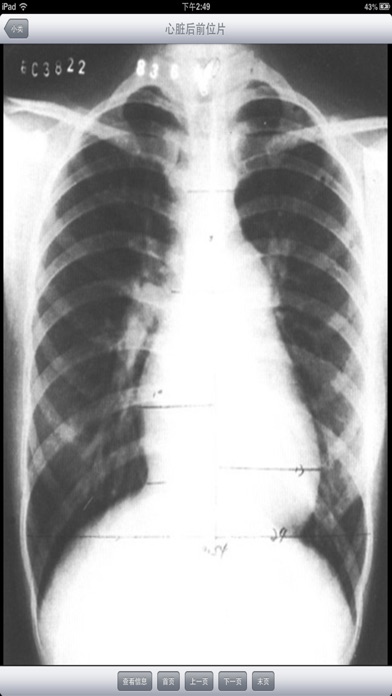

随着医疗卫生事业的发展,各种医疗仪器层出不穷的涌现,给临床诊断工作带来了极大的帮助,尤其是B超、CT、X光等影像学检查的应用,大大的提高了临床诊断的正确符合率和准确性。 基层诊断医生对影像知识缺乏了解,不能结合临床有重点的剖析,正确地加以辨别,诊断难以深刻,而且易忽略不典型病变,产生误诊、漏诊;另外,基层医生缺乏必要的影像读片知识,从而影像了诊断水平的提高。 影像诊断系统能够指导各级医生如何识别B超、CT、X光等临床表现,分析各种疾病的影像特征,做出更符合临床的影像诊断。每一张影像都配有表现和评述,是医生和医学院校的学生学习影像诊断入门的必备软件。